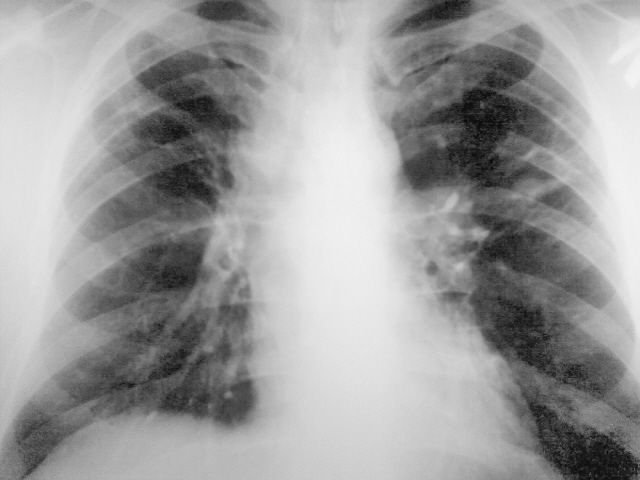

Потупил с диагнозом инфильтр tbs с поражением в/гр и периферич л/у. Болеет около месяца. Не контактен, пов t до 38. Менингиальные знаки 3+. Умер через 30 часов, на вскрытии...

Заподозрить еще как можно. Доказать, проблемно. Но подняв литературу узнал что картина типична для хронического... на фоне которого развивается... Обратите внимание на кисты слева, а справа формируется аналогичная.

Кавернозный туберкулез, ослабление иммуннитета. Присоединение неспецифической инфекции привело к сепсису и меннингиту, смерть, скорее, от менингита. Смущает эмфизема легких, но на легочную дистрофию не тянет. Конечно, досужие вымыслы. На КТ данных за медиастинит нет, кистовидные полости с толстыми стенками. СПИД всё бы объяснил.

Совершенно верно! Имеет место хронический лейкоз на фоне которого пневмония с распадом, кисты справа следствие таких же пневмоний. Остается вопрос почему кровь не набрали с самого начала.

Возраст около 45, точно не помню. На снимках еще стоял. Пока все мимо. Напомню увеличены в/гр и периферические л/у.

Неет причина смерти совсем иная. Уточню тут две патологии, одна обуславливает другую.

Раз увеличены все л/у, может, лейкоз.